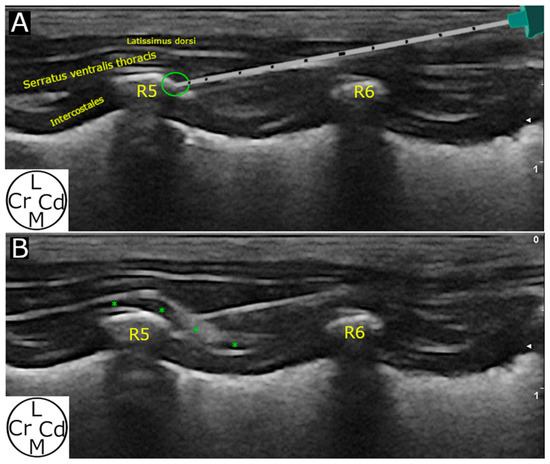

2.2.1. Ultrasound-Guided Technique

3.2.2. Ultrasound-Guided Technique